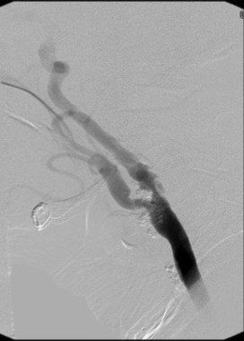

Karotis arter hastalığının tanısında en sık kullanılan testlerin başında karotis ultrason gelmektedir. Karotis ultrason ile darlığın yapısı ve ciddiyeti hakkında bilgi edinilir. Eğer karotis ultrason yetersiz kalır veya ciddi darlık saptanırsa müdehale öncesinde karotis anjiografisi yapılır.

Resim. Karotis anjioda darlık